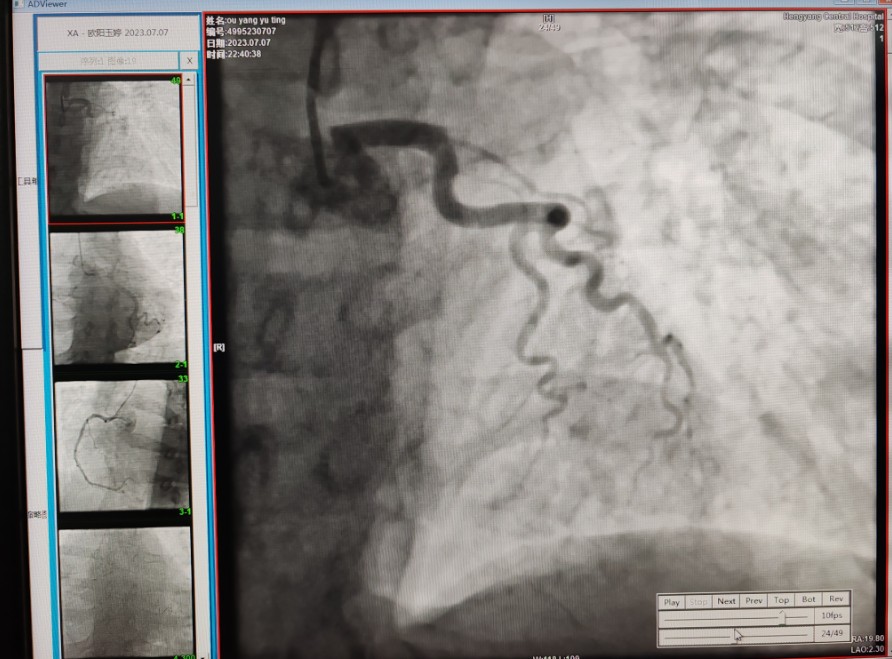

22:29分患者經(jīng)院內(nèi)綠色通道送達(dá)導(dǎo)管室,手術(shù)由雷剛副主任醫(yī)師主刀,楊繼賀副主任醫(yī)師為第一助手,介入技師及護(hù)士密切配合,聞?dòng)嵍鴣淼内w慶禧主任醫(yī)師坐鎮(zhèn)協(xié)調(diào)指揮。22:37分手術(shù)開始,冠脈造影顯示心臟上最重要的一條冠狀動(dòng)脈-前降支開口齊頭閉塞,血管粗大且血栓高負(fù)荷,非??简?yàn)介入術(shù)者的手術(shù)能力,一旦發(fā)生冠脈無復(fù)流或操作不慎血栓帶入回旋支導(dǎo)致循環(huán)崩潰,病人幾乎無生還希望;此時(shí),患者手術(shù)臺(tái)上仍持續(xù)胸痛,且血氧飽和度在高流量吸氧狀態(tài)下不到80%,雷剛副主任醫(yī)師一方面指揮鎮(zhèn)靜鎮(zhèn)痛及抗心衰治療,一方面緊急啟用IABP(主動(dòng)脈球囊反搏),然后精細(xì)操控細(xì)如發(fā)絲的介入導(dǎo)絲迅速通過病變,并予冠脈球囊擴(kuò)張、冠脈內(nèi)溶栓、抗痙攣藥物使用、植入冠脈支架,最終成功開通“罪犯”血管,且無手術(shù)并發(fā)癥發(fā)生,整個(gè)過程張弛有度、快慢結(jié)合、一氣呵成。患者術(shù)后胸痛明顯好轉(zhuǎn),血氧飽和度上升至96%,術(shù)后1天轉(zhuǎn)出監(jiān)護(hù)病房,第3天拔出IABP,目前已康復(fù)出院。